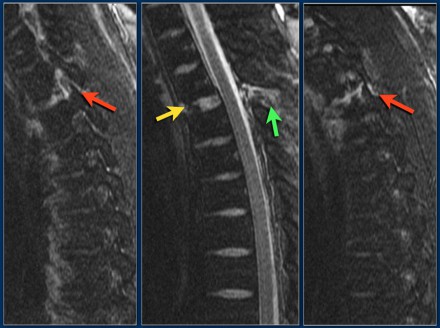

Look at the images.

What are the findings?

Then scroll to the next images.

The findings are:

- Vertebral bodies show marrow edema as a result of a fracture.

- Torn flaval ligament (yellow arrow).

- Fractures through the posterior elements (red arrows).

The TLICS-score is high, because there is distraction and injury to the PLC.